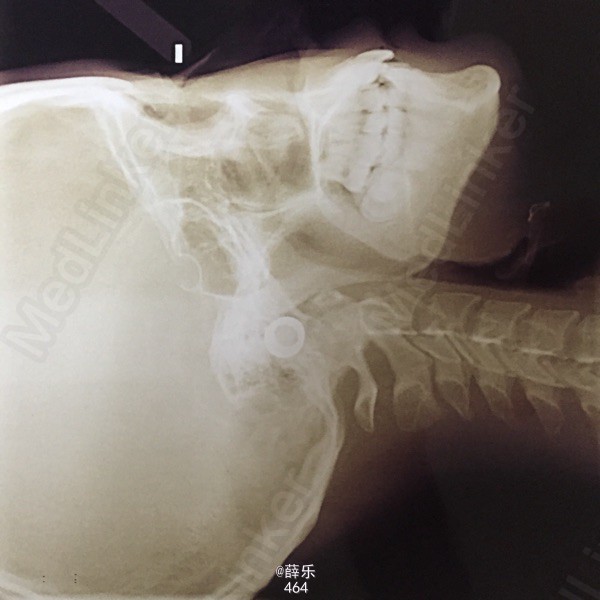

查体 辅查

恒牙列,牙列式17~27,37~47。双侧磨牙中性关系,上下牙列中度拥挤,13、23唇侧低位,38、48近中阻生,侧观呈直面型,上下前牙较直立

诊断:安氏1类错牙合伴牙列拥挤 建议:正畸治疗 处理:1.取研究模型 2.血液检查 3.全景片+侧位片+面像检查 4.约会诊